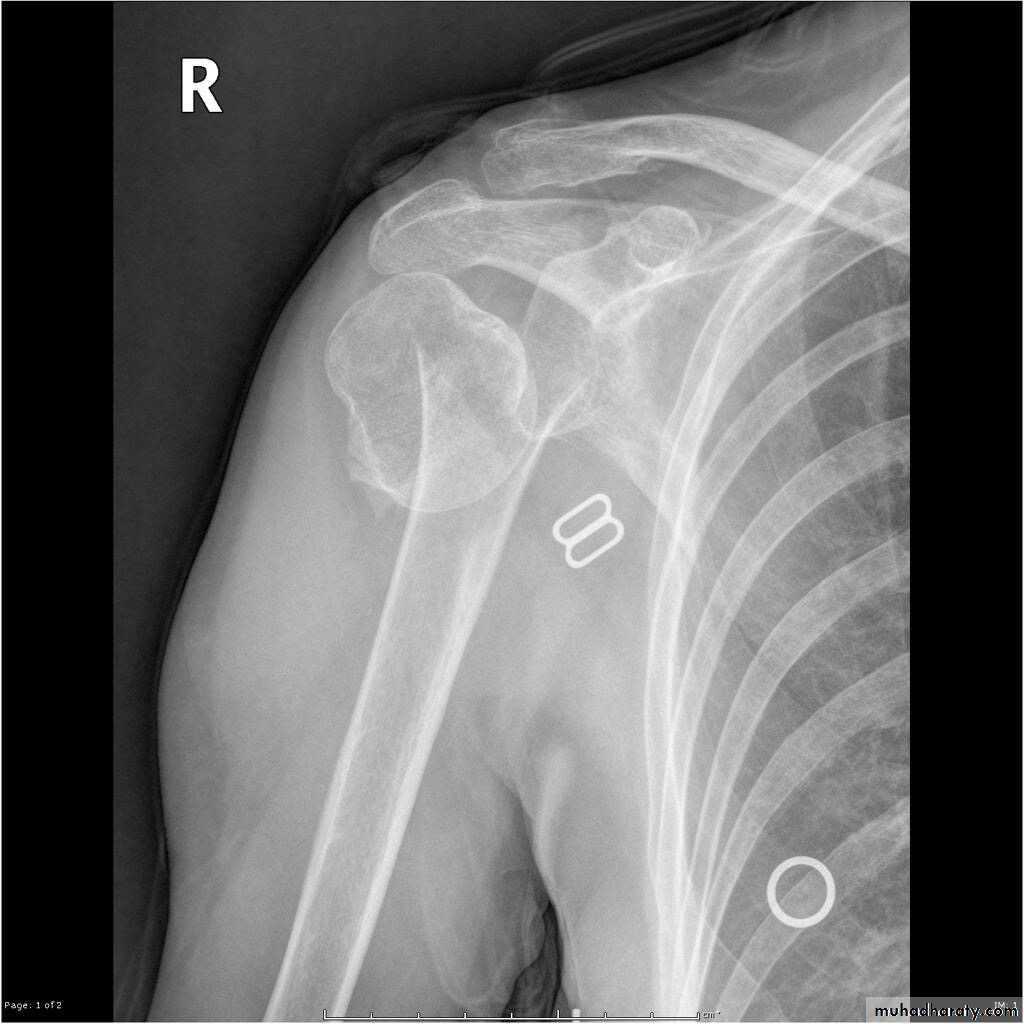

X RAY

27

28